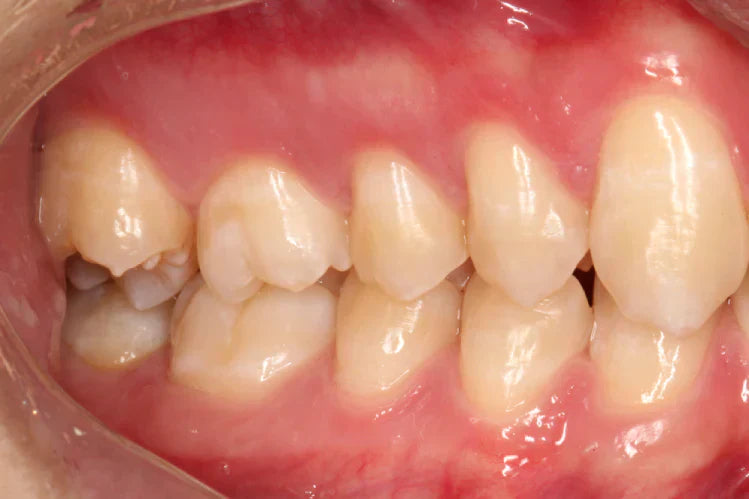

The posterior teeth, also known as teeth located at the back of the mouth are primarily responsible for chewing and grinding. Posterior teeth feature large sizes, are stronger than anterior teeth (incisors and canines), and are flat with cusps (bumps) designed for food breaking.

Adults possess eight premolars and twelve molars, including wisdom teeth at the end of the rows. The posterior teeth are crucial for chewing, maintaining the jaw's natural shape, and promoting dental health.

These two teeth, or bicuspids, are between the canines and molars. Because of their design, they are useful for tearing and crushing food. Premolars are transitional teeth that possess canine-molar characteristics.

The largest and strongest teeth are the molars, the broadest teeth in the mouth. They have broad surfaces with multiple cusps for grinding food. Adults usually have 12 molars, including wisdom teeth.